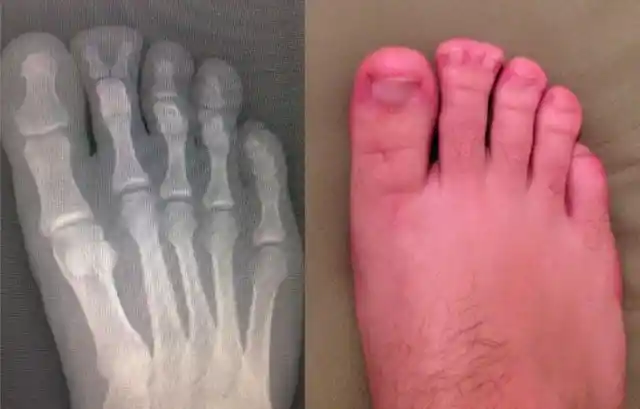

Two Bones Too Many

What makes humanity so wonderful is that we are able to embrace our differences and live together in harmony—at least that’s what we aim to do. Every now and then, we notice traits or physical features in others that we don’t have ourselves. Sometimes we encounter traits that we’ve never encountered before.

Take this foot, for example, the owner of this foot probably thought it was just a rarity that he had two fingernails on one of his toes, but in reality, he had a whole extra bone at the tip of his toe, as if the end of his toe were splitting in two. Wow!